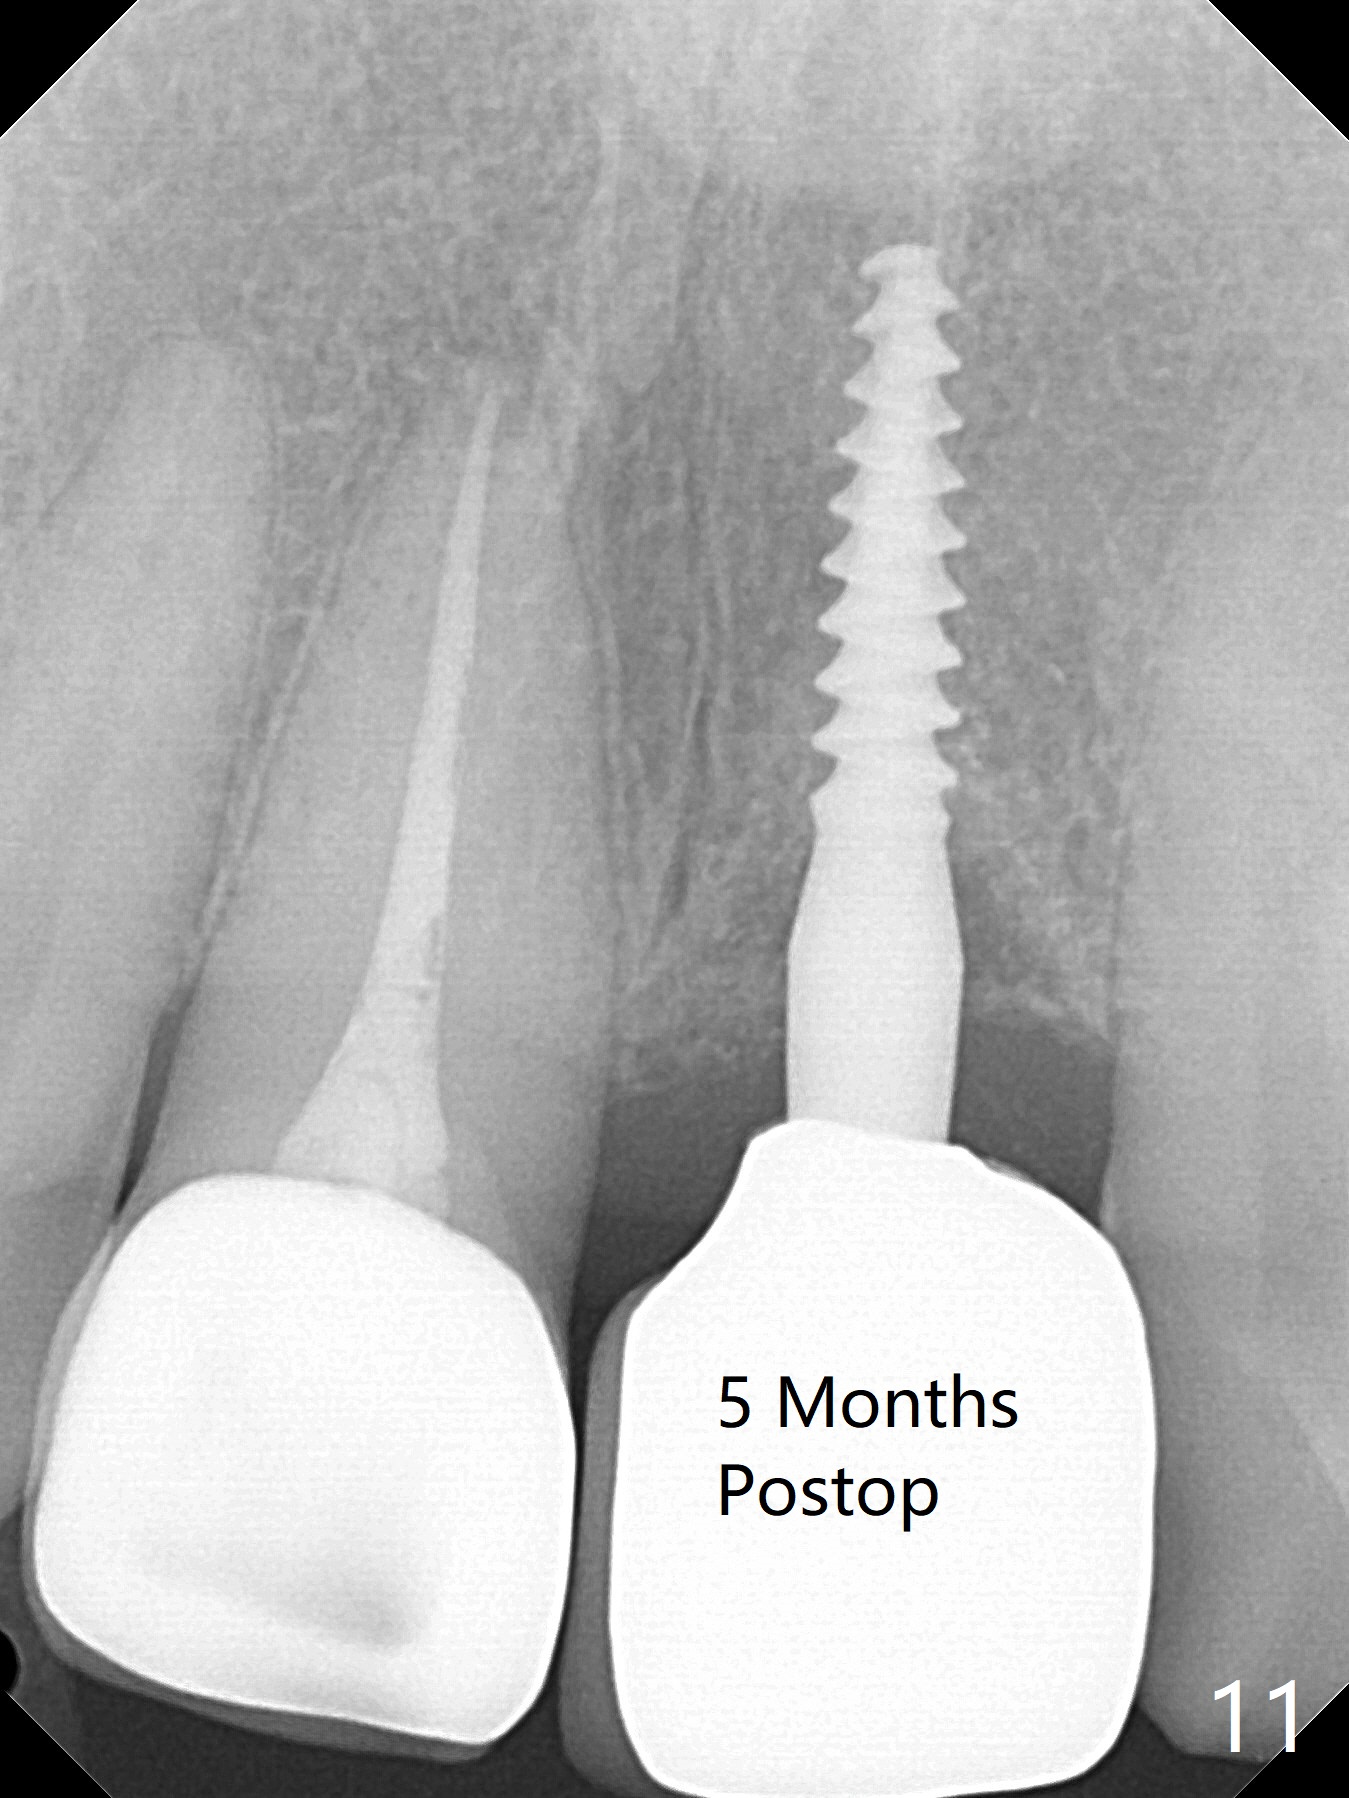

Except the depth, a 2.5x10 mm mini implant is placed with precision (in trajectory) at #9 (Fig.1-5). Confidence using surgical guide for the narrow ridge is enhanced due to placement of two digits against the buccal and palatal plates for tactile sensation. The depth issue is related to overprep with 2.2 mm drills. The torque is <15 Ncm. The immediate provisional is bonded to the neighboring teeth for retention. It appears that smaller drills should be made for guided surgery (such as 1.5 and 2.0 mm). The immediate provisional looks acceptable buccal and occlusal 3 weeks postop (Fig.6,7), although the palatal gingiva is erythematous (Fig.8, which is common after use of drill for access (tissue laceration), OHI offered). Three months postop (Fig.9), the palatal gingiva looks healthy (data not shown), while there is no bone loss around the implant (Fig.10). It remains the same 5 months postop (immediately post cementation, Fig.11) and 3,11 months post cementation (Fig.12,13). The labial gingiva is healthy (Fig.14), while the palatal one is less erythematous and edematous (Fig.15) than earlier (Fig.8).